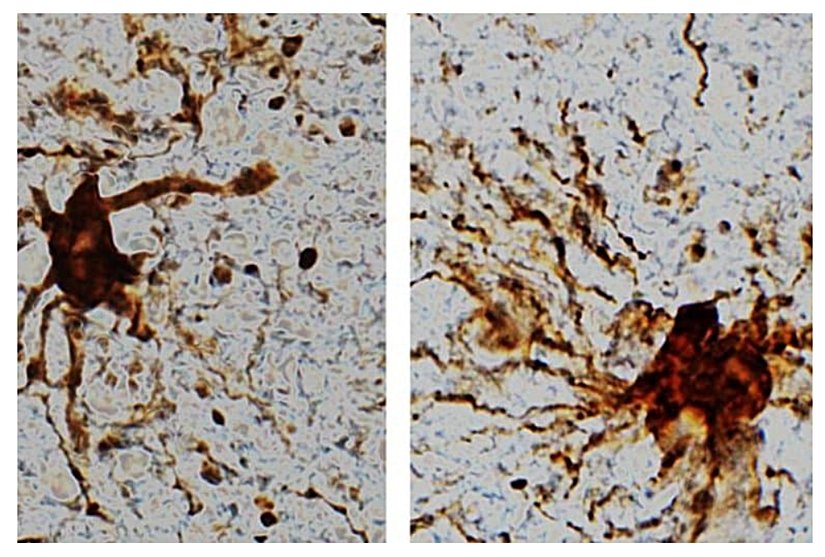

Ölüm sonrasında geçen süre boyunca ifade edimi artan, yani daha fazla miktarda okunarak proteine dönüştürülen bu "zombi genler", özellikle de spesifik bir hücre tipine aitti: gliyal hücreler adı verilen, nöronları destekleyen, koruyan ve tamir eden hücrelere! Araştırmacılar, ölümden saatler sonra gliyal hücrelerin büyüdüğünü ve kol benzeri uzantılar oluşturduğunu gözlemlediler.

Ölümden sonra meydana gelen gliyal hücre büyümesi, yangısal (enflamatuvar) olmaları ve görevlerinin oksijen yoksunluğu ya da felç gibi beyin hasarlarından sonra ortalığı temizlemek olduğu düşünülünce, ölümden sonra artan bu faaliyetleri çok da şaşırtıcı değil.